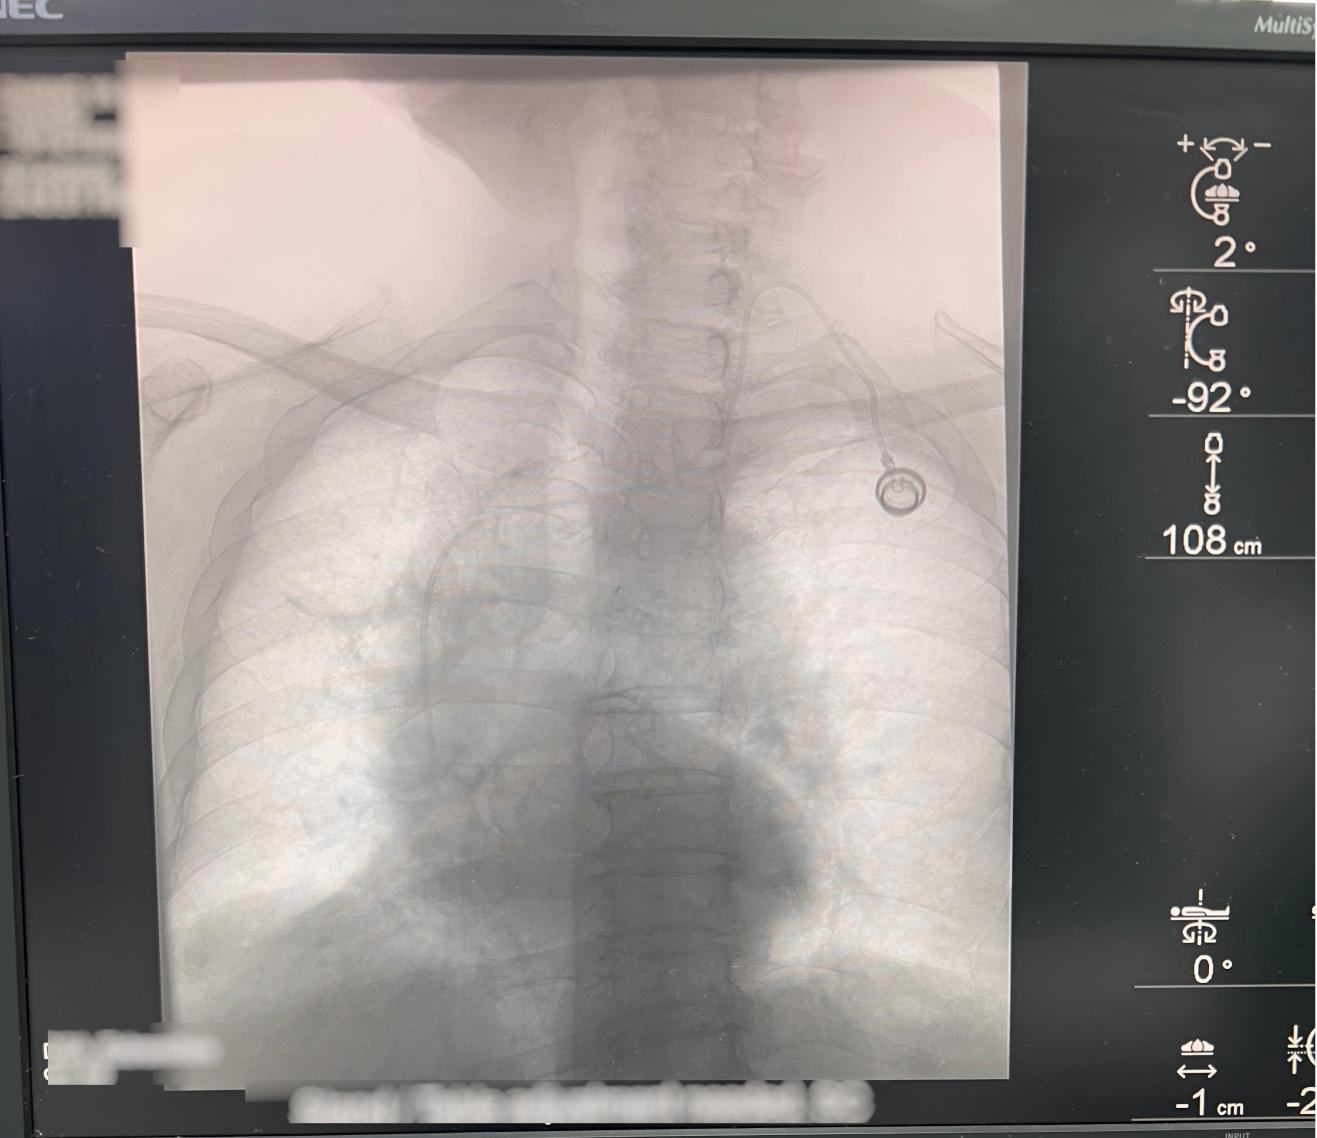

近日,北京中医药大学东方医院外四科成功为数名患者实施了输液港置入手术。该手术的顺利开展,标志着科室在静脉输液治疗领域取得了新的突破,为患者提供了更加安全、便捷的治疗选择。

对于一些需要长期接受静脉输液治疗的患者,传统的输液方式不仅给患者带来了频繁穿刺的痛苦,还增加了感染和血管损伤的风险。在手术过程中,曹刚医生带领的手术团队凭借丰富的临床经验和精湛的技术,精准操作,便顺利完成了输液港的置入。术后,患者生命体征平稳,无任何不适反应。目前,患者已恢复良好,正在接受后续的治疗。

输液港的置入为患者提供了一条长期、安全、可靠的静脉通道,减少了患者反复穿刺的痛苦,提高了治疗的便利性和舒适性。同时,它还降低了感染和血栓形成的风险,对于保障患者的治疗效果和生活质量具有重要意义。